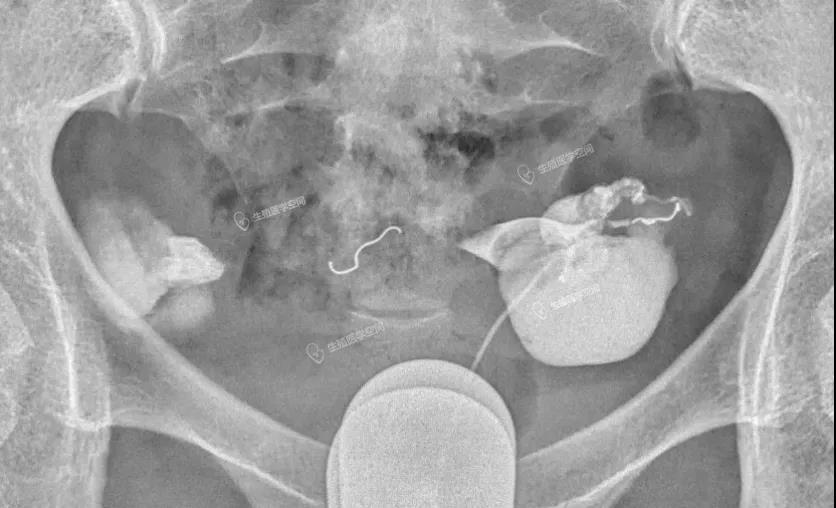

图6:栓塞后没做造影看看效果,术后1个月和3个月复查弹簧圈都出现位置和形态改变

是一位做了双侧输卵管“致密栓塞”后,做试管婴儿还发生宫外孕。